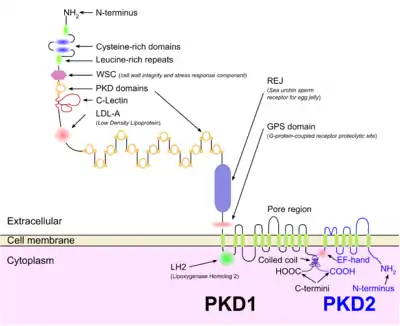

ADPKD is genetically heterogeneous with two genes identified: PKD1 (chromosome region 16p13.3; around 85% cases) [12]and PKD2 (4q21; around 15% cases).[13][14][1] Several genetic mechanisms probably contribute to the phenotypic expression of the disease.[1] Although evidence exists for a two-hit mechanism (germline and somatic inactivation of two PKD alleles) explaining the focal development of renal and hepatic cysts,[15][16] haploinsufficiency is more likely to account for the vascular manifestations of the disease.[17][18] Additionally, new mouse models homozygous for PKD1 hypomorphic alleles 22 and 23 and the demonstration of increased renal epithelial cell proliferation in PKD2 +/− mice suggest that mechanisms other than the two-hit hypothesis also contribute to the cystic phenotype.[1]

In many patients with ADPKD, kidney dysfunction is not clinically apparent until 30 or 40 years of life.[5] However, an increasing body of evidence suggests the formation of renal cysts starts in utero.[24] Cysts initially form as small dilations in renal tubules, which then expand to form fluid-filled cavities of different sizes.[24] Factors suggested to lead to cystogenesis include a germline mutation in one of the polycystin gene alleles, a somatic second hit that leads to the loss of the normal allele, and a third hit, which can be a renal insult that triggers cell proliferation, and an injury response.[25] Due to numerous similarities between the pathophysiology of ADPKD and the pathophysiology of the renal response to injury, ADPKD has been described as a state of aberrant and persistent activation of renal injury response pathways.[26] In the progression of the disease, continued dilation of the tubules through increased cell proliferation, fluid secretion, and separation from the parental tubule lead to the formation of cysts.[27][28]

ADPKD, together with many other diseases that present with renal cysts, can be classified into a family of diseases known as ciliopathies.[29] Epithelial cells of the renal tubules, including all the segments of the nephron and the collecting ducts (with the exception of intercalated cells) show the presence of a single primary apical cilium.[30] Polycystin-1, the protein encoded by the PKD1 gene, is present on these cilia and is thought to sense the flow with its large extracellular domains, activating the calcium channels associated with polycystin-2, the product of gene PKD2,[31] as a result of the genetic setting of ADPKD as explained in the genetics sub-section above.